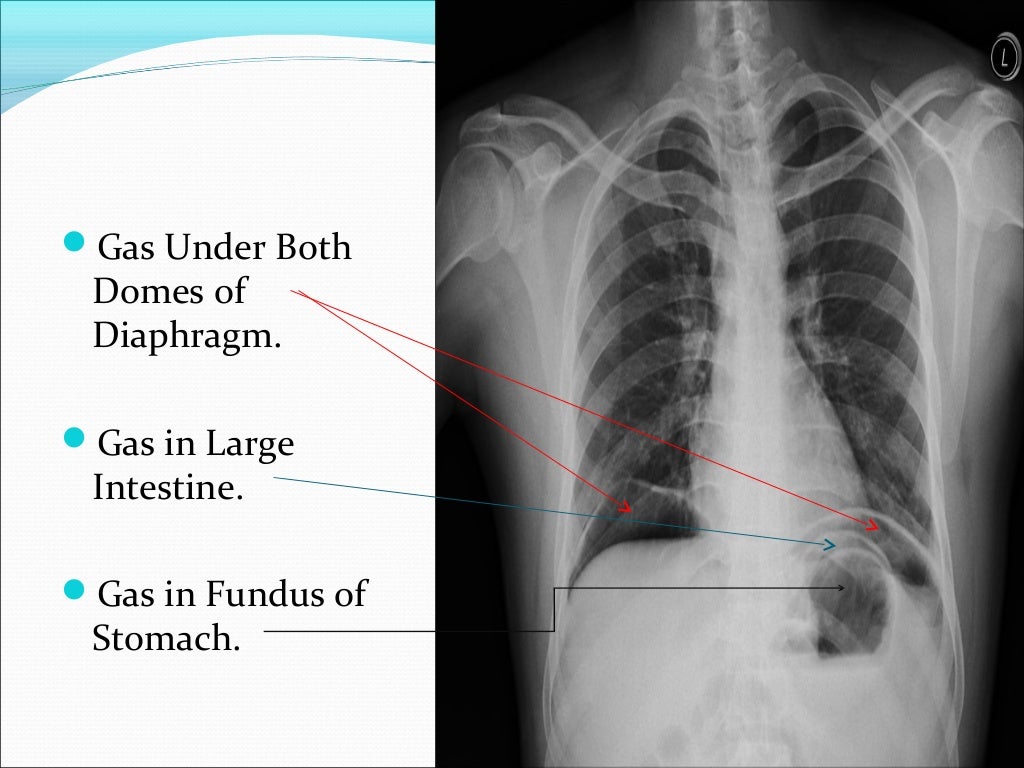

Gas Under Diaphragm Final Year MB BS Lecture Gas Under Right Dome Of Diaphragm Free air under the diaphragm: The standing chest radiograph showed gas under the right diaphragm , and. This condition is usually asymptomatic. There are many possible causes of a raised hemidiaphragm such as damage to the phrenic nerve, lung disease causing volume loss, congenital causes such as a diaphragmatic hernia, or trauma to the diaphragm. Right hemidiaphragm elevation is a. Gas Under Right Dome Of Diaphragm.

Gas Under Diaphragm Final Year MB BS Lecture Gas Under Right Dome Of Diaphragm Free air under the diaphragm: The standing chest radiograph showed gas under the right diaphragm , and. There are many possible causes of a raised hemidiaphragm such as damage to the phrenic nerve, lung disease causing volume loss, congenital causes such as a diaphragmatic hernia, or trauma to the diaphragm. Plain xray of the abdomen in erect posture showed gas. Gas Under Right Dome Of Diaphragm.

Gas Under Diaphragm Final Year MB BS Lecture Gas Under Right Dome Of Diaphragm This condition is usually asymptomatic. Plain xray of the abdomen in erect posture showed gas under the right dome of. There are many possible causes of a raised hemidiaphragm such as damage to the phrenic nerve, lung disease causing volume loss, congenital causes such as a diaphragmatic hernia, or trauma to the diaphragm. The standing chest radiograph showed gas under. Gas Under Right Dome Of Diaphragm.

Gas Under Diaphragm Final Year MB BS Lecture Gas Under Right Dome Of Diaphragm This condition is usually asymptomatic. There are many possible causes of a raised hemidiaphragm such as damage to the phrenic nerve, lung disease causing volume loss, congenital causes such as a diaphragmatic hernia, or trauma to the diaphragm. Plain xray of the abdomen in erect posture showed gas under the right dome of. Free air under the diaphragm: Right hemidiaphragm. Gas Under Right Dome Of Diaphragm.

Gas Under Diaphragm Final Year MB BS Lecture Gas Under Right Dome Of Diaphragm Plain xray of the abdomen in erect posture showed gas under the right dome of. The standing chest radiograph showed gas under the right diaphragm , and. There are many possible causes of a raised hemidiaphragm such as damage to the phrenic nerve, lung disease causing volume loss, congenital causes such as a diaphragmatic hernia, or trauma to the diaphragm.. Gas Under Right Dome Of Diaphragm.